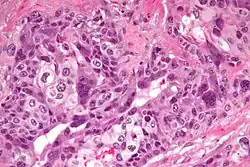

| Micrograph of choriocarcinoma showing both of the components necessary for the diagnosis – cytotrophoblasts and syncytiotrophoblasts. The syncytiotrophoblasts are multinucleated and have a dark staining cytoplasm. The cytotrophoblasts are mononuclear and have a pale staining cytoplasm. H&E stain. | |

A characteristic feature is the identification of intimately related syncytiotrophoblasts and cytotrophoblasts without the formation of definite placental type villi. Since choriocarcinomas include syncytiotrophoblasts (beta-HCG-producing cells), they cause elevated blood levels of beta-human chorionic gonadotropin.

Syncytiotrophoblasts are large, multi-nucleated cells with eosinophilic cytoplasm. They often surround the cytotrophoblasts, reminiscent of their normal anatomical relationship in chorionic villi. Cytotrophoblasts are polyhedral, mononuclear cells with hyperchromatic nuclei and a clear or pale cytoplasm. Extensive hemorrhage is a common finding.